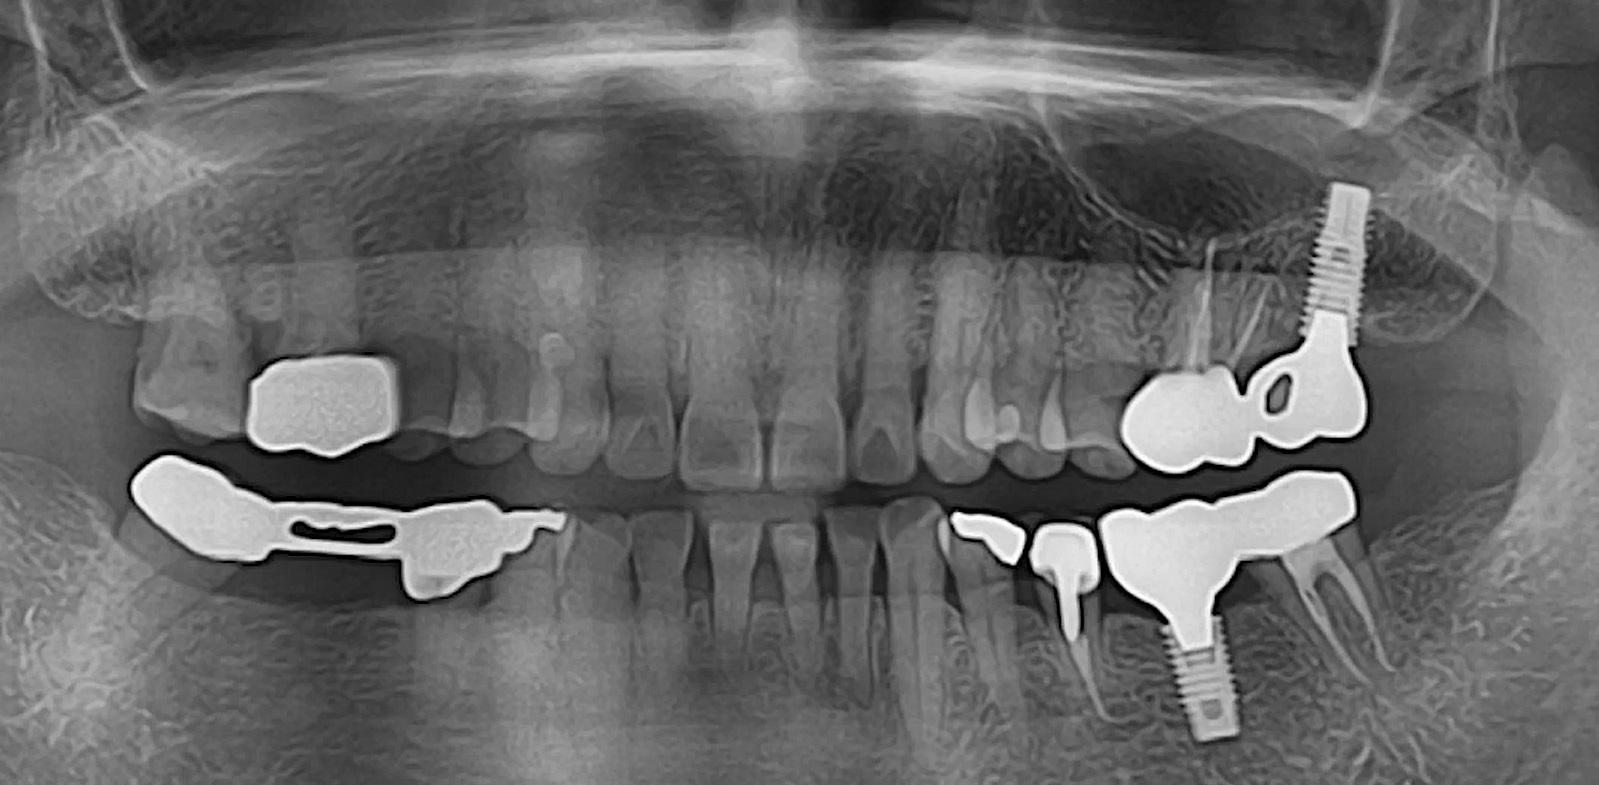

Contour Restoration of Over- Resected Mandibular Angle and Lower Border by Reduction Mandibuloplasty Using Three- Dimensional Planning and Computer-Aided Design and Manufacturing Custom-Made Titanium Implants